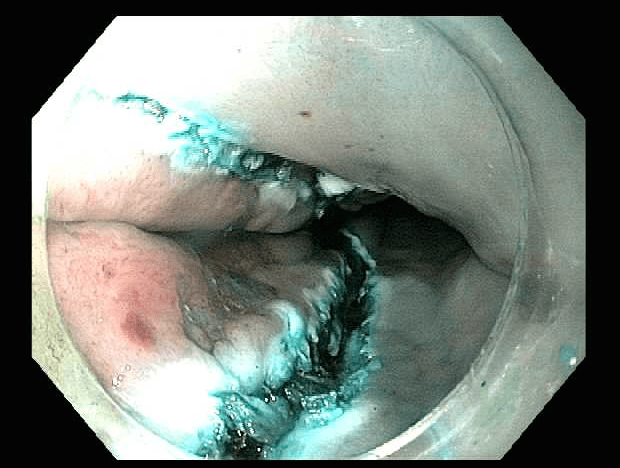

Esophagus with early squamous cell cancer, shown with high-definition white lightEsophagus with early squamous cell cancer, shown with high-definition white light

This case (Figures 1-5) illustrates endoscopic resection of an early squamous cell esophageal cancer from the mid-esophagus. The patient presented with non-cardiac chest pain, which was thought to be unrelated to this early stage neoplasm. The ESD procedure removed the lesion with clear lateral and deep margins. The resection specimen measured 2.5 x 1.9 x 0.4 cm.